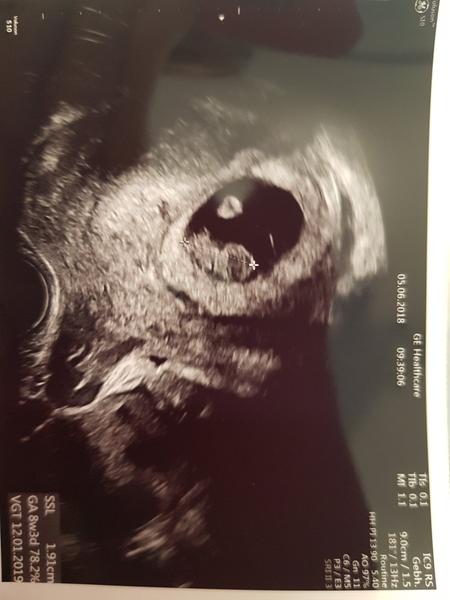

Ahoj holky, tak včera na ultrazvuku. Byla jsem z toho trochu špatná, měla jsem být 8+1 a podle ultrazvuku 7+3, přitom zezačátku to hezky odpovídalo, tak doufám, že to moje neustálý zvracení prcka nějak neohrozí☹. Má jen 11 mm. Ivanka měla v 7+5 14,3 mm.....ach jo, zase to moje porovnávání.... Ale srdíčko tluče jako o závod. Termín porodu zhruba 14.1.2019:-)